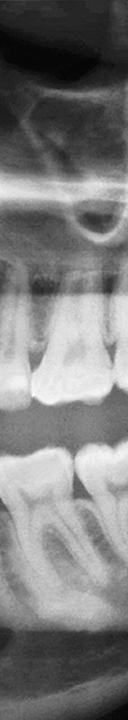

또한 사랑니가 삐뚤어지게 자라거나 매복 되어 있는 경우에는 더욱 더 심각한 문제를 일으킬 수 있었어요. 올바르게 자라지 않아 정상적으로 위치하고 있는 주변 치아에 영향을 주게 되어 치아 배열이 불규칙해질 수 있으며 또한 수평으로 누워서 잇몸에 완전히 덮여 사랑니가 아예 보이지 않는 경우, 또는 일부분만 덮여 있는 부분 매복처럼 다양한 형태로 나타날 수 있었어요. 사랑니가 매복 되어 있는 경우에는 염증이 생길 수 있어 볼, 편도선, 림프절 등이 부어올라 극심한 통증을 느끼게 되었어요. 또한 매복 되어 있는 사랑니의 형태가 심각한 경우에는 턱 뼈의 변형까지 생길 수 있었어요.

이처럼 사랑니는 여러가지 문제를 일으켜 치아 건강을 악화 시킬 수 있으니 대부분의 치과에서는 사랑니 발치를 권해드리고 있었어요. 하지만 사랑니가 매복 되어 있는 경우 신경과 가까운 곳에 사랑니가 위치하고 있기 때문에 발치를 하는 과정에서 신경을 건드릴 수 있어 숙련된 의료진에게 치료 받는 것이 중요하였어요.

매복 사랑니의 경우 발치 시간도 많이 걸리고 주변 신경을 건드리지 않고 발치를 해야 하기 때문에 난이도가 있는 시술로 부작용이 생기지 않게 치료 받는 것이 중요하므로 신경 위치와 주변 치아의 상태를 정밀하게 검사 가능하고 숙련된 실력으로 사랑니 발치를 할 수 있는 의료진이 있는지 꼭 확인하신 후 치과를 선택하시기를 바라겠어요.

신논현역치과에서는 3D CT 장비로 촬영을 하여 사랑니의 매복 상태와 사랑니 부근의 신경처럼 중요한 부분을 정밀 검사를 통해 확인하고 사랑니 발치에 대한 안전한 치료 계획을 세운 후 발치를 진행하고 있었어요. 개인 구강의 상태에 따라 사랑니의 모양, 매복 형태 및 정도가 모두 다르기 때문에 아름드리에서는 그에 알맞는 방법으로 사랑니 발치를 환자 구강 상태에 맞게 진행하고 있었어요.